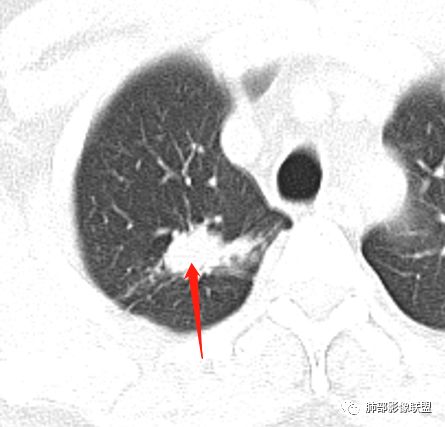

病史:男性,49岁,反复咳嗽月余,伴左胸痛;   影像:形态奇特,长毛刺,疑多灶,支气管阻塞不明显,毛刺不明显,纵膈窗密度不均,其内似见低密度,有凹陷,膨隆不除外,纵膈窗胸膜有点增厚。诊断:结核(右上肺)鉴别:不符合,无钙化,无胸腔积液;腺癌(无淋巴结)。处置:寻找结核相关检查,肿标,纤支镜,增强。

患者中年男性,主诉:咳嗽  胸痛。  胸CT:右肺上叶尖段占位,病灶位于支气管外,病灶周围部分区域可见毛玻璃影,病灶边缘不规则,部分区域可见平直,胸膜牵拉(无胸膜凹陷),柔软长毛刺,分叶,纵隔窗病灶没可见低密度区,左肺尖可见一点状病灶,病灶整体考虑良性疾病:感染性病变(结核?),感染后机化?。恶性病变待除外。

右肺上叶结节,边缘平直为主,病灶比较散,周周似乎有卫星病灶,边缘有胸膜牵拉,从粗到细,左肺尖奕有卫星灶,综合考虑结核。

晨读:患者中年男性,反复咳嗽1月余,伴左胸部疼痛1周就诊。胸部CT:右肺上叶尖后段不规则结节,见长毛刺、胸膜牵拉、条索影,周围见卫星灶。未见明显淋巴结肿大,符合结核病变。鉴别其他。但其病灶位于右肺,主诉左胸痛,是误写,还是?

一米阳光:    晨读,右上肺结节影,形态不规则,边缘平直,部分凹陷,长软毛刺,胸膜牵拉,周围卫星灶。考虑结核。鉴别腺癌,部分边缘彭隆

傅昌瑜:  男,49岁,反复咳嗽1月余,伴左侧胸痛1周。右肺上叶尖段结节,边缘平直、凹陷,周周似乎有卫星病灶,边缘有胸膜牵拉,从粗到细,左肺尖见小点状病灶,考虑良性病变,结核可能性大。

小飞:  晨读:右肺上叶不规则结节灶,沿支气管走形分布,边缘平直,U型凹陷,脊柱侧有少许磨玻璃影,左肺尖少许斑点灶,综合考虑结核。

右肺上叶病灶两部分

纵隔窗提示内侧部分密度不够实

边缘平直、凹陷为主,部分膨隆

内部小点状影提示可能支气管腔内粘液栓

左肺尖及右肺病灶附近见小斑点,边界尚清

1、病灶整体形态不是类圆形,边缘凹陷、平直为主,长轴重建可能更明显,长索条,附近卫星灶,左肺尖有类似小高密度影;按常规:首先要考虑结核